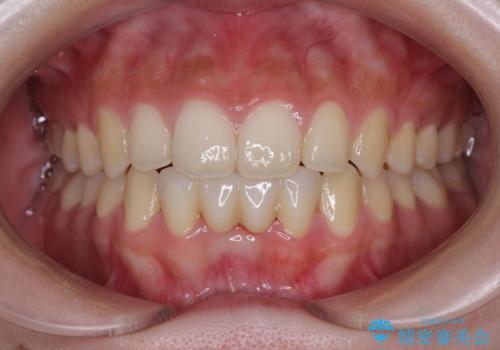

[ 前歯開咬 ] 前歯が噛んでいない マウスピース矯正治療

担当医 大元洋佑

![[ 前歯開咬 ] 前歯が噛んでいない マウスピース矯正治療の症例 治療後](https://seimitsushinbi.jp/wp/wp-content/uploads/2022/11/IMG_2488-500x350.jpg?v=1668218373)